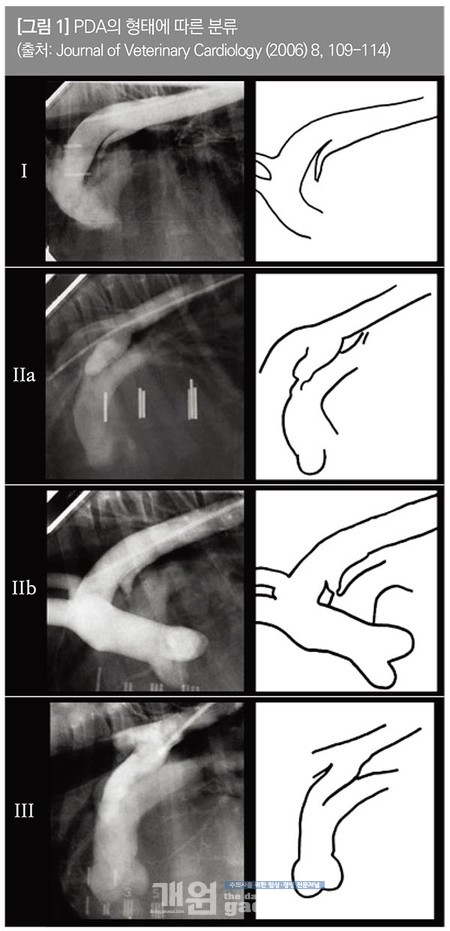

동맥관은 크기와 형태와 따라 다양하게 분류되는데, type I의 경우 ductus의 직경이 작고, 대동맥에서 폐동맥으로 점차 직경 감소하는 형태, type II의 경우 폐동맥으로 들어가기 전에 급격하게 ductus의 직경이 작아지는(50% 이상 감소)는 형태로 좁아지는 모양에 따라 type IIa와 type IIb로 분류된다.

마지막으로 원통 형태로 ductus의 직경 변화없이 이어지는 형태를 type III로 분류하며, 한 문헌에 따르면 type IIa와 IIb가 높은 비중(87%)을 차지한다고 보고되어 있다[그림 1].